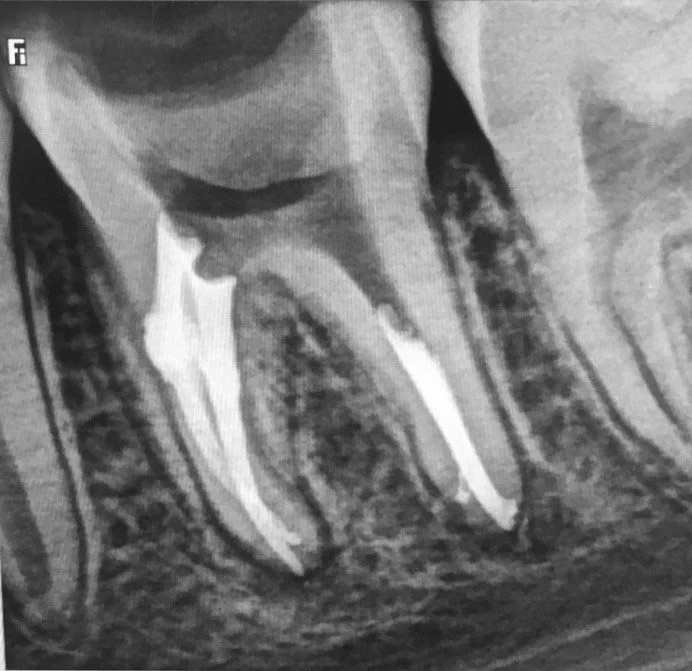

Usunięcie ankera zacementowanego na cement kompozytowy oraz reendo d.45 wraz z wykonaniem odbudowy adhezyjnej.